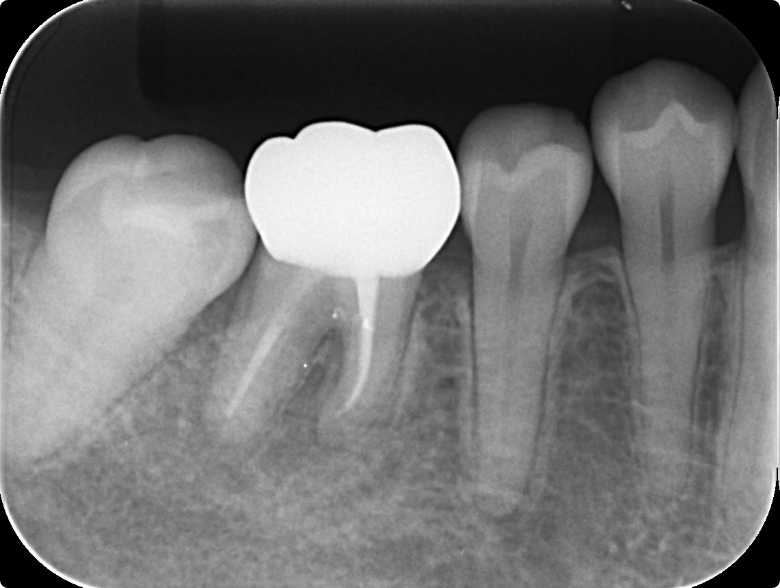

奥歯の根管治療を行った症例

BEFORE

AFTER

症例概要

年代、性別

49歳女性

主訴

左上の歯茎から膿がでている

診断

根尖性歯周炎

治療内容

感染根管治療、ファイバーポストを用いた支台築造、フルジルコニアクラウン装着

治療期間

2ヶ月程度

治療リスク

噛み合わせの状態によっては歯根破折を起こすことがある

治療費用

242,000円(税込)